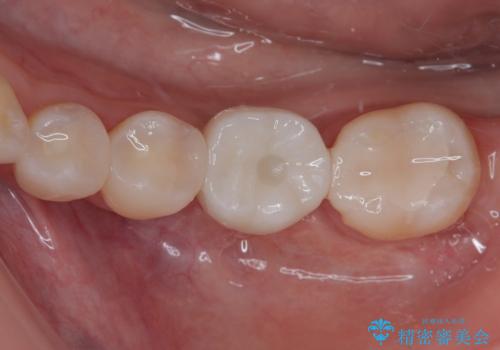

- ブリッジの歯のないところにインプラントを入れて、銀歯を白くやり替えたいと来院された患者様です。

歯の欠損している箇所にはインプラント治療をし、銀歯と仮詰めの部分はセラミックインレーにて補綴することとしました。